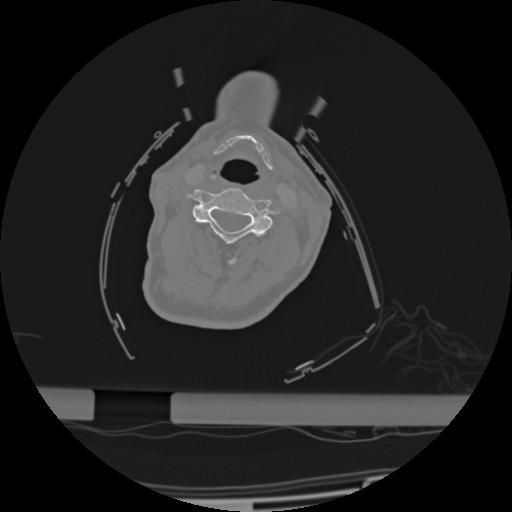

22 ANGIO,CE,Vol,0.5,ANGIO,,